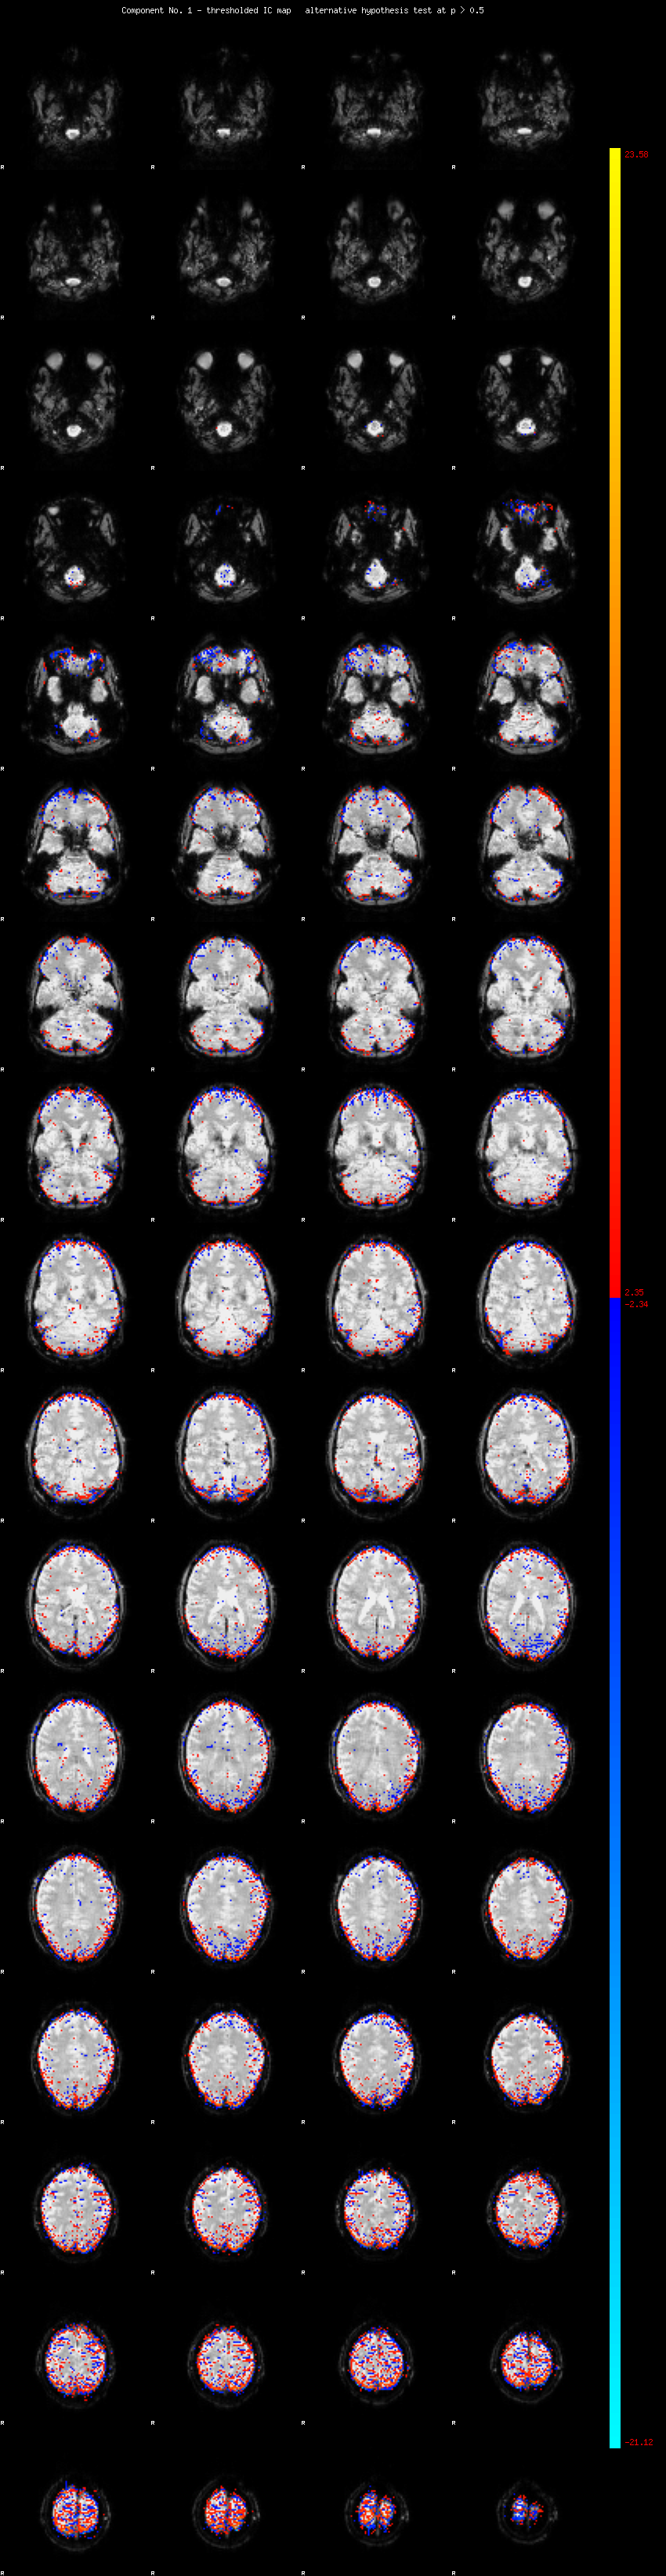

MELODIC Component 1

8.08 % of explained variance;     5.36 % of total variance